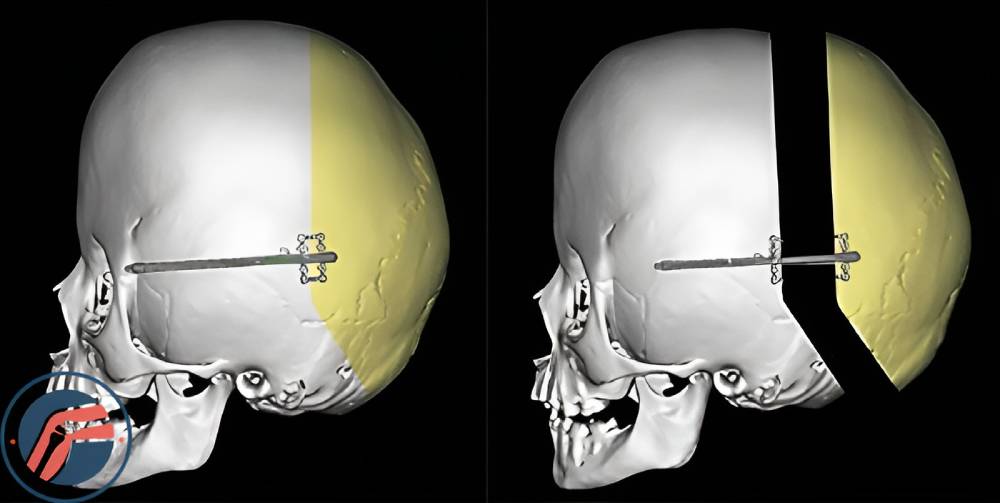

دیستراکشن جمجمه (Cranial Vault Distraction یا Cranial Distraction): این جراحی برای گسترش بخشی از جمجمه، معمولاً پشت جمجمه استفاده می شود. در حین عمل، جراح تکهای از جمجمه را بر میدارد، سپس با استفاده از ابزارهای مخصوص پزشکی که به وسیله پیچ محکم شده است، شرایطی بوجود میآورد که جمجمه افزایش اندازه بدهد و بزرگتر شود. هنگامی که استخوان به اندازه کافی رشد کرد، جراح پیچ ها و ابزارهای استفاده شده را خارج میکند.

این روش برای درمان تغییر فرم های شدید و پیچیده و در مواردی که چندین درز بسته شده عامل ایجاد اختلال هستند به کار میرود.